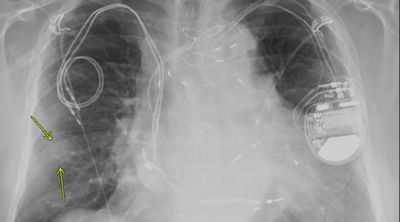

Безопасное выполнение МРТ у пациентов с кардиостимуляторами и ИКД

Согласно исследованию, опубликованному в журнале Radiology: Cardiothoracic Imaging, обследования МРТ могут быть безопасно выполнены у пациентов с кардиологическими устройствами, несовместимыми с МРТ, в том числе у тех, кто зависит от кардиостимулятора или у которых нет электродов.

Миллионы людей во всем мире полагаются на имплантированные сердечные устройства, такие как кардиостимуляторы и имплантируемые кардиовертеры-дефибрилляторы (ИКД), чтобы контролировать аномальные сердечные ритмы. …